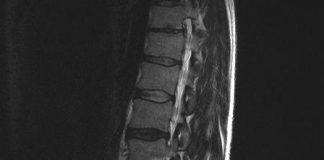

Nieuwe herniabehandeling (PTED) voorlopig vergoed

De afkorting staat voor Percutaan Transforminale Endoscopische Descectonomie. Dat betekent dat de zwelling van de hernia wordt verwijderd via je een klein sneetjeaan de...